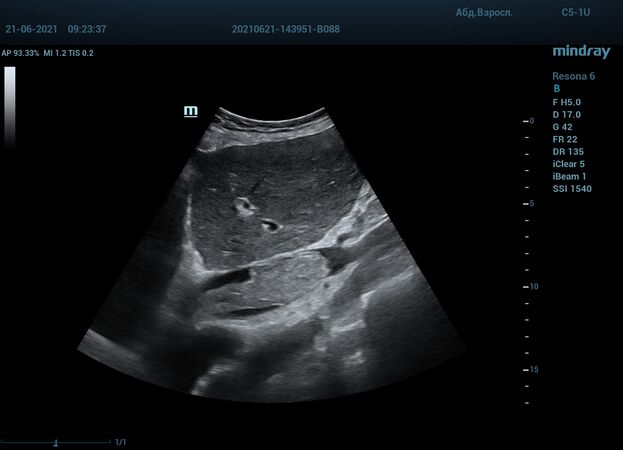

Интересный случай из практики нашего врача-аппликатора. Использовался экспертный ультразвуковой прибор Mindray Resona 6, стандартные заводские пресеты и автоматическая оптимизация iTouch. В эхокардиографии всегда помогает колорайзинг, чаще всего используется оранжевый оттенок. Пациент обследуется перед оперативным лечением по поводу онкологии почки. Вены нижних конечностей у данного пациента без особенностей, сжимаемы и проходимы. Казалось бы, проблема тромбоза миновала но в процессе эхокардиографического исследования, при сканировании нижней полой вены в субкостальном сечении, определяется эхогенное образование. Образование на месте просвета нижней полой вены. Вена расширена, эхогенное включение проникает в правое предсердие. По краю тромба в цветопотоковой визуализации определяется кровоток. Онкологическое заболевание почки осложнилось тромбозом почечной вены, с распространением тромба в нижнюю полую вену и правое предсердие. Изюминку добавляет то, что в других эхокардиографических сечениях тромб совершенно не виден.